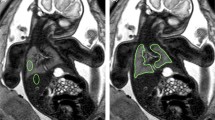

Recently, several groups reported normal reference values of fetal lung volumes between 18 and 37 GW (Table 1). Except for some specialized prenatal care centers, this method has not been accepted as standard in the detection and quantification of pulmonary hypoplasia. This is mainly due to the complicated and time-consuming postprocessing, as well as the need for the involvement of an examiner, experienced in fetal anatomy and the technique of MR volumetry. Automated, computerized lung volume quantification (Thayyil et al. 2008) would help to overcome some of these problems. Currently, it is difficult to automatically create appropriate masks, which accurately define the organ boundaries and prevent the inclusion of other organs, mainly due to the inhomogeneous signal properties of the fetal lung, which are often overlapping with extrapulmonary structures. Additionally, the changing signal characteristics of the fetal lungs, especially in the condition of hypoplasia, would lead to inconsistent and unreliable results. Therefore, the manual tracing method is actually the only and most reliable tool in the fetal MR biometry of fetal lung volumes. Still, its accuracy and diagnostic value depend on skill and experience of the examiner. This can be easily and quickly achieved, as the anatomy of the fetal lung is visualized in an unequivocal way (Figure 4, 5, 6).

In order to achieve the most reliable results, it is important to rule out movement as a major source of error in fetal lung volumetry (Fig. 9). For obvious reasons, the detection of motion-degraded images should be already performed by the time of sequence acquisition as this may guarantee at least one axial sequence of acceptable quality for volumetry. This mainly applies to artifacts caused by fetal motion, as they are easily detectable.

The problem of fetal motion in fetal lung volumetry: multiplanar reconstruction of the original data sensitively detects fetal and/or maternal motion, even if the in-plane/axial image appears of quite good quality (upper row). Repeated acquisition of T2-weighted sequences increases the chance of a nonmotion-degraded dataset with a smooth reconstruction (lower row)

However, maternal breathing movements may result in significant motion of the fetus in the craniocaudal axis and thereby to the repeated acquisition of one slice position. Especially, while assessing axial images, this bias is difficult to realize. A fast and secure way to prevent this error is the reconstruction of the sequence in the coronal and sagittal plane (Fig. 9). Most of the available image processing software packages provide a multiplanar reconstruction tool, which is easily accessible. The appearance of large “steps” of the fetal thoracic body contour in the reconstructed image may serve as a good indicator of maternal or fetal motion (Fig. 9). In this way, misregistrations of the volumetry data may be avoided and accuracy of the measurements improved.

The manual delineation of the pleural contours of the fetal lung is still the most reliable way to segment this organ. The clear delineation of fetal pulmonary tissue may be challenging in certain anatomical regions. In order to compare the volumetry data with the reference literature, the hilar structures (pulmonary vessels, bronchial airways) should be avoided (Fig. 10). Segmentation of the lung base is often challenged by partial volume artifacts (due to the diaphragmatic domes). Additionally, the hyperintense adrenal cortex and retroperitoneal fat make it difficult to differentiate between the bordering tissue types (Fig. 5). A consistent way to measure in this area is important as incorrect segmentation at the lung base causes the greatest error.